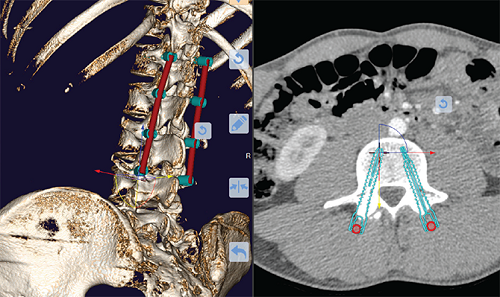

+ Đặt vít nhanh qua nhiều cấp độ: chiều dài đinh vít, góc vào lý tưởng, độ sâu của đinh vít, chiều dài của thanh nẹp và độ cong của nó, loại thanh nẹp phù hợp với mỗi bệnh nhân,...

+ Tự động định vị các vít và and lồng qua nhiều tầng đốt sống

Dụng cụ vặn vít cho phép bác sĩ chọn từ nhiều loại vít và chiều dài khác nhau trong kho dữ liệu. Trên mô hình xương 3D đã được phân đoạn, bác sĩ có thể chọn thêm phần đốt sống và cạnh xương sống cần thiết.

Vít chân trục giờ đây được tự động lắp vào mô hình 3D ở vị trí tiêu chuẩn. Bác sĩ có thể điều chỉnh, xoay, di chuyển, khoan vít hoặc chuyển hoàn toàn sang loại vít khác.

Mỗi điều chỉnh được tự động hiển thị trong tất cả các chế độ xem mô hình 3D và lát cắt 2D. Khi làm việc ở chế độ lập kế hoạch kết hợp 2D và 3D, một mô tả điều chỉnh tự động sẽ được hiển thị. Điều này cho phép bác sĩ thử nhiều phương án phẫu thuật, tìm giải pháp tốt nhất cho mỗi bệnh nhân và đánh giá nó theo các khía cạnh khác nhau.

Sau khi chọn tất cả các cạnh đốt sống và cuống sống cần thiết, bác sĩ có thể tự động lắp tất cả các vít và thanh nẹp cần thiết.

Xác định trước chiều dài của thanh nẹp.